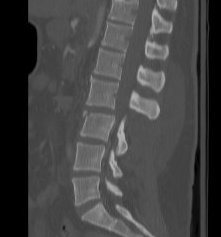

CT

Look for canal compromise

- cord signal change

- kyphotic deformity

Retropulsed fragments

- always between pedicles

- typically one or two main fragments (saloon door)

- assess canal compromise